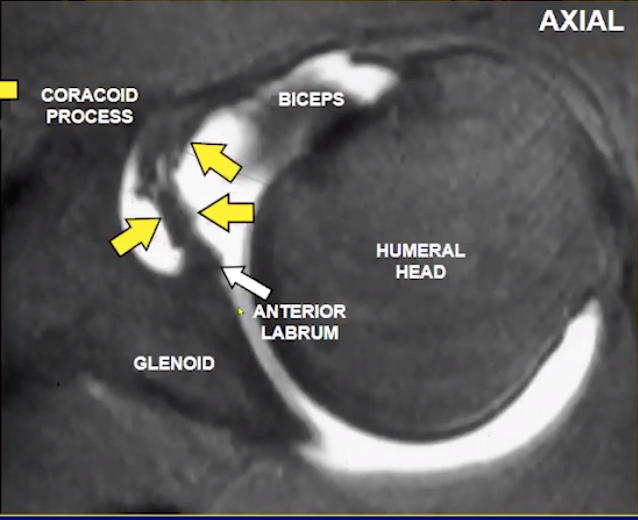

Bony Bankart lesion

• > 25% glenoid surface bone loss is an indication for surgery

• should comment on this in report

Buford Complex

• Absent anterior-superior labrum + cord like MGHL